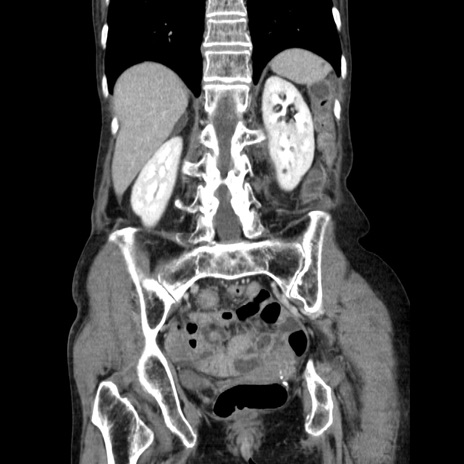

症例25(冠状断像)

【症例】80歳代女性

【主訴】胸のつかえ感

【現病歴】約9時間前に食後から胸のつかえた感じあり、嘔吐あり、来院。

【既往歴】胃癌(全摘)、胆摘、虫垂炎

【身体所見】心窩部に圧痛あり、反跳痛なし。

【データ】WBC 5700、CRP 0.05